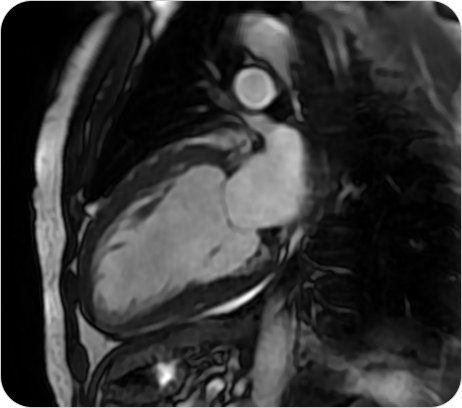

Resonancia Magnética Cardíaca

La resonancia magnética cardíaca es un estudio no invasivo y altamente especializado que permite obtener imágenes detalladas del corazón en movimiento. Brinda información precisa sobre la estructura, función, tejidos y vasos del corazón, sin utilizar radiación.

¿PARA QUE SE UTILIZA?

- Estudio de última generación para evaluar el corazón con altísima precisión, sin radiación. Diagnóstico completo de función, tejidos y circulación cardíaca.

- Evaluar la función del corazón y de las válvulas cardíacas.

Detectar infartos antiguos o recientes y analizar el daño al miocardio. - Diagnóstico de miocardiopatías (hipertrófica, dilatada, restrictiva, etc.).

- Detección de inflamación (miocarditis) o fibrosis del músculo cardíaco.

- Evaluación prequirúrgica o seguimiento de enfermedades cardíacas complejas.

- Estudio de tumores cardíacos o enfermedades congénitas.

¿POR QUÉ ES UN ESTUDIO DESTACADO?

- Estudio de última generación para evaluar el corazón con altísima precisión, sin radiación. Diagnóstico completo de función, tejidos y circulación cardíaca.

- Evaluar la función del corazón y de las válvulas cardíacas.

Detectar infartos antiguos o recientes y analizar el daño al miocardio. - Diagnóstico de miocardiopatías (hipertrófica, dilatada, restrictiva, etc.).

- Detección de inflamación (miocarditis) o fibrosis del músculo cardíaco.

- Evaluación prequirúrgica o seguimiento de enfermedades cardíacas complejas.

- Estudio de tumores cardíacos o enfermedades congénitas.

Resonancia Magnética Cardíaca

La resonancia magnética cardíaca es un estudio no invasivo y altamente especializado que permite obtener imágenes detalladas del corazón en movimiento. Brinda información precisa sobre la estructura, función, tejidos y vasos del corazón, sin utilizar radiación.

¿PARA QUE SE UTILIZA?

- Estudio de última generación para evaluar el corazón con altísima precisión, sin radiación. Diagnóstico completo de función, tejidos y circulación cardíaca.

- Evaluar la función del corazón y de las válvulas cardíacas.

Detectar infartos antiguos o recientes y analizar el daño al miocardio. - Diagnóstico de miocardiopatías (hipertrófica, dilatada, restrictiva, etc.).

- Detección de inflamación (miocarditis) o fibrosis del músculo cardíaco.

- Evaluación prequirúrgica o seguimiento de enfermedades cardíacas complejas.

- Estudio de tumores cardíacos o enfermedades congénitas.

¿POR QUÉ ES UN ESTUDIO DESTACADO?

- Estudio de última generación para evaluar el corazón con altísima precisión, sin radiación. Diagnóstico completo de función, tejidos y circulación cardíaca.

- Evaluar la función del corazón y de las válvulas cardíacas.

Detectar infartos antiguos o recientes y analizar el daño al miocardio. - Diagnóstico de miocardiopatías (hipertrófica, dilatada, restrictiva, etc.).

- Detección de inflamación (miocarditis) o fibrosis del músculo cardíaco.

- Evaluación prequirúrgica o seguimiento de enfermedades cardíacas complejas.

- Estudio de tumores cardíacos o enfermedades congénitas.